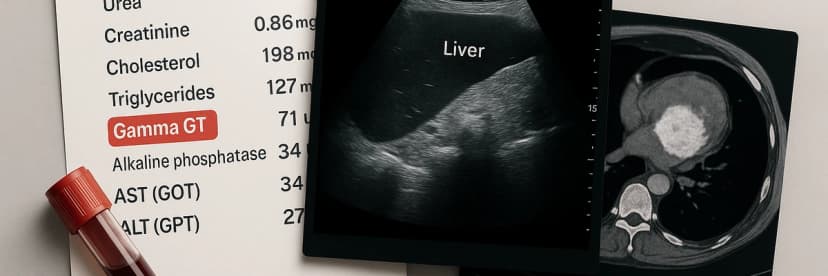

Gamma GT élevé : analyses, imagerie et suivi médical. Découvrez les examens indispensables pour identifier la cause et agir sur votre santé.